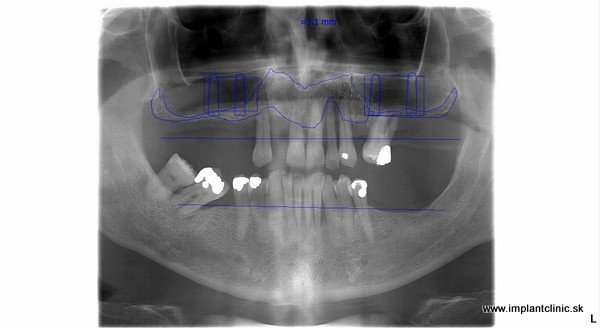

Snímok pacienta po ošetrení

Druhá návšteva: implantácia. Z dôvodu oslabenej čeľustnej kosti sa naplánovalo do vrchnej čeľuste 9 zubných inplantátov, 6 zubných implantátov do sánky, dostavba kosti, sinus lift, extrakcie. Implantácia do oboch čeľustí prebehla počas jedného sedenia v lokálnej anestéze. Hneď po implantácii boli pacientovi nasadené fixne dočasné mostíky, ktoré sú pre maximálnu stabilitu a pevnosť vystužené titánovou konštrukciou.